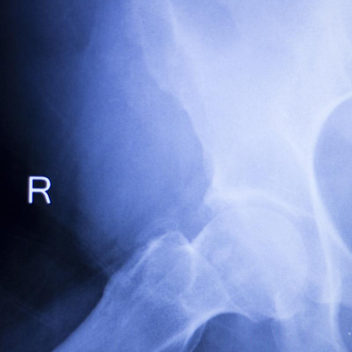

A. 锁骨骨折, B髓内钉治疗